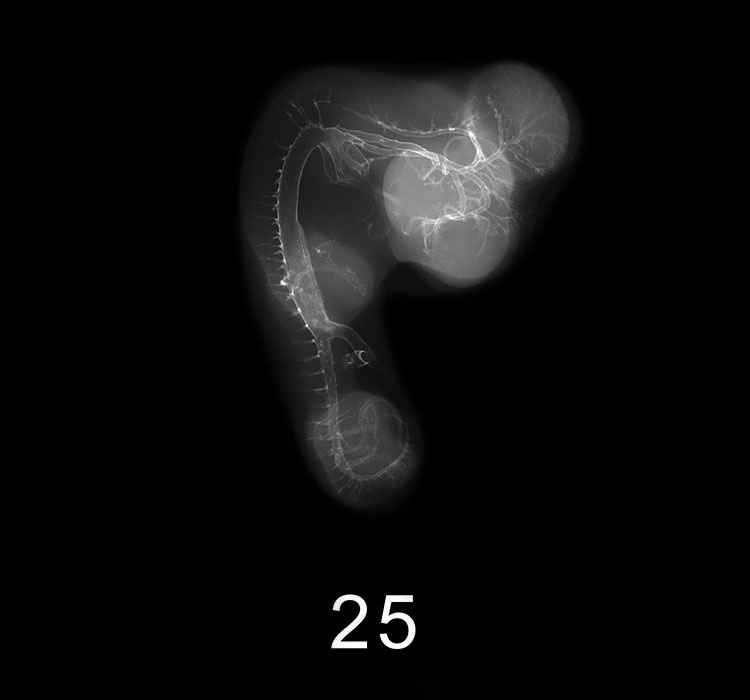

Chick Embryo Microangiography

Images listed by Hamburger-Hamilton (HH) Stage

Hamburger-Hamilton (HH) stages are a system used by those who study chick embryo development to describe the apparent maturity of the developing chick from laying of the egg to hatching. An embryo is assigned an HH stage (numbered from 1 to 46) based on its physical shape and visible features (morphology). This staging system is not dependent on the chronological age nor the size of the embryo, which are susceptible to variations due to breed, temperature during incubation, season, and time between egg laying and incubation. The stages, are in a sense, arbitrary levels of maturity based on multiple physical features. For example, embryos that might have different ages or sizes might be assigned the same HH stage based on their external appearance due to the natural variation which occurs between individuals or due to differing conditions during incubation.